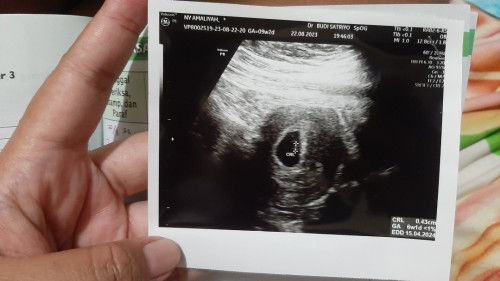

Hamil anak pertama terus kemarin keluar flek darah merah lumayan bikin deg2an, terus langsung periksa ke spog alhamdulillah kata dokternya sehat terus dikasih liat ada kelip2 di monitor itu katanya bakal jantung utun. Kalo ngitung hpht UK 9w1d tapi pas periksa ternyata baru 6w1d bunds. Semoga bunda2 dan dede utun sehat selalu#firstmom